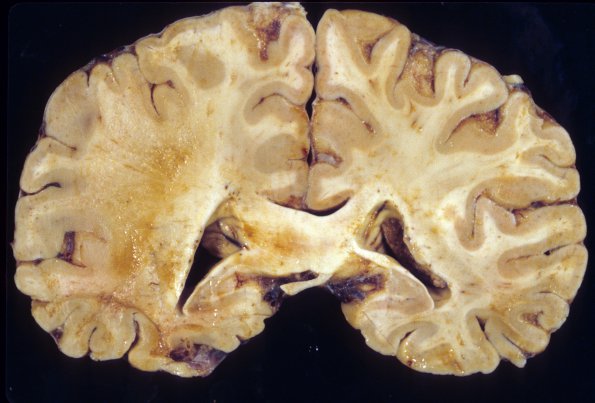

3A4 PML (Case 3) 1

Areas of involvement of the white matter may be extensive.